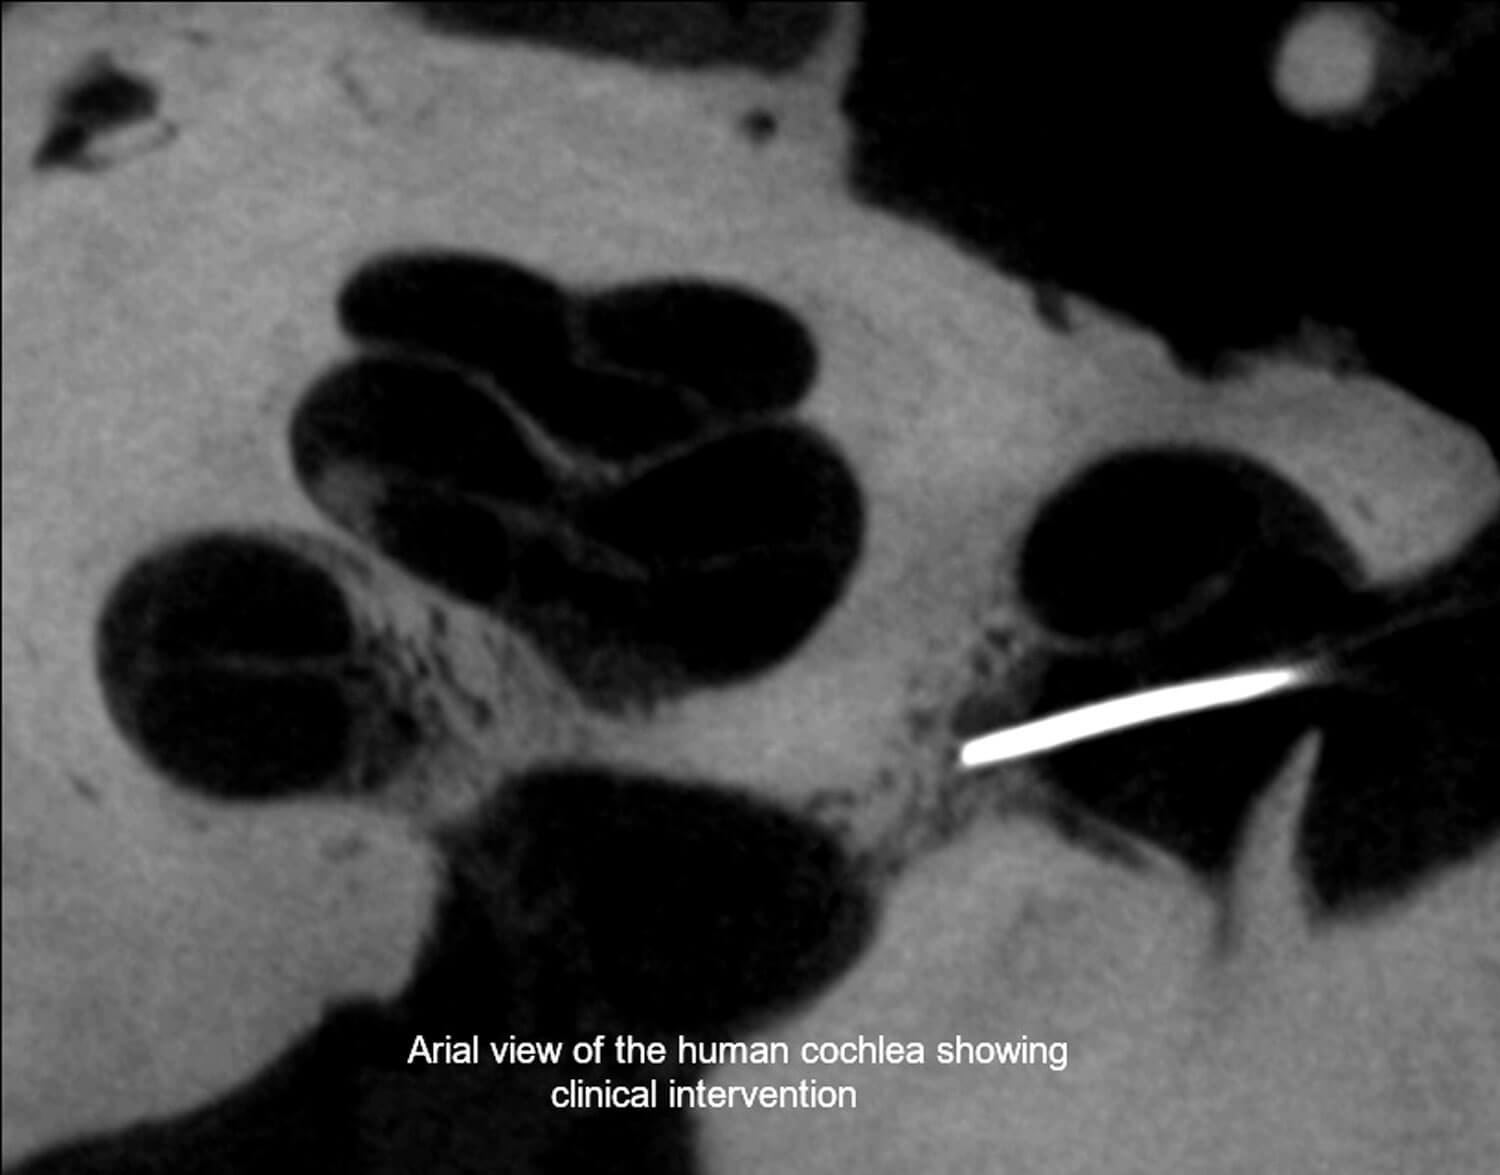

An international team of surgeons and scientists has, for the first time, validated safe surgical access to the central core of the human cochlea in a study funded by Rinri Therapeutics, a biotechnology company developing regenerative cell therapies for sensorineural hearing loss (SNHL). The research is published in Scientific Reports.

The team from Guy’s and St Thomas’ NHS Foundation Trust in London and the universities of Uppsala (Sweden), Sheffield (UK), Nottingham (UK) and Western University (Canada) has proven and confirmed a secure clinical pathway to the inner ear, which will enable the application of a range of regenerative therapies to restore hearing.

The human cochlea lies in the base of the skull, encased by the hardest bone in the human body. This has hampered the progress of discovering new treatments for hearing loss. Using a detailed representation of the microanatomy of the peripheral auditory neural structure, surgeons have now been able to reach the human cochlea safely with a routine surgical approach.

Marcelo Rivolta, Professor of Sensory Stem Cell Biology at the University of Sheffield and Founder of Rinri Therapeutics said: “Until now this region of the inner ear has been inaccessible in humans. This means that the pioneering advanced therapies to repair the auditory nerve, which have already proved successful in animal models, have been hampered by limited anatomical knowledge and the lack of a safe access to Rosenthal’s canal - the compartment that houses the auditory neurons within the central core of the cochlea.

Gerry O’Donoghue, Professor of Otology and Neurotology at the University of Nottingham and Clinical Advisor to Rinri Therapeutics, said: “The inaccessibility of the human cochlea has hampered the progress of curative treatments for SNHL to date. These findings however will enable the safe delivery of regenerative therapeutics to their target structures within the relatively impenetrable human cochlea, de-risking future clinical interventions and paving the way for clinical trials.”